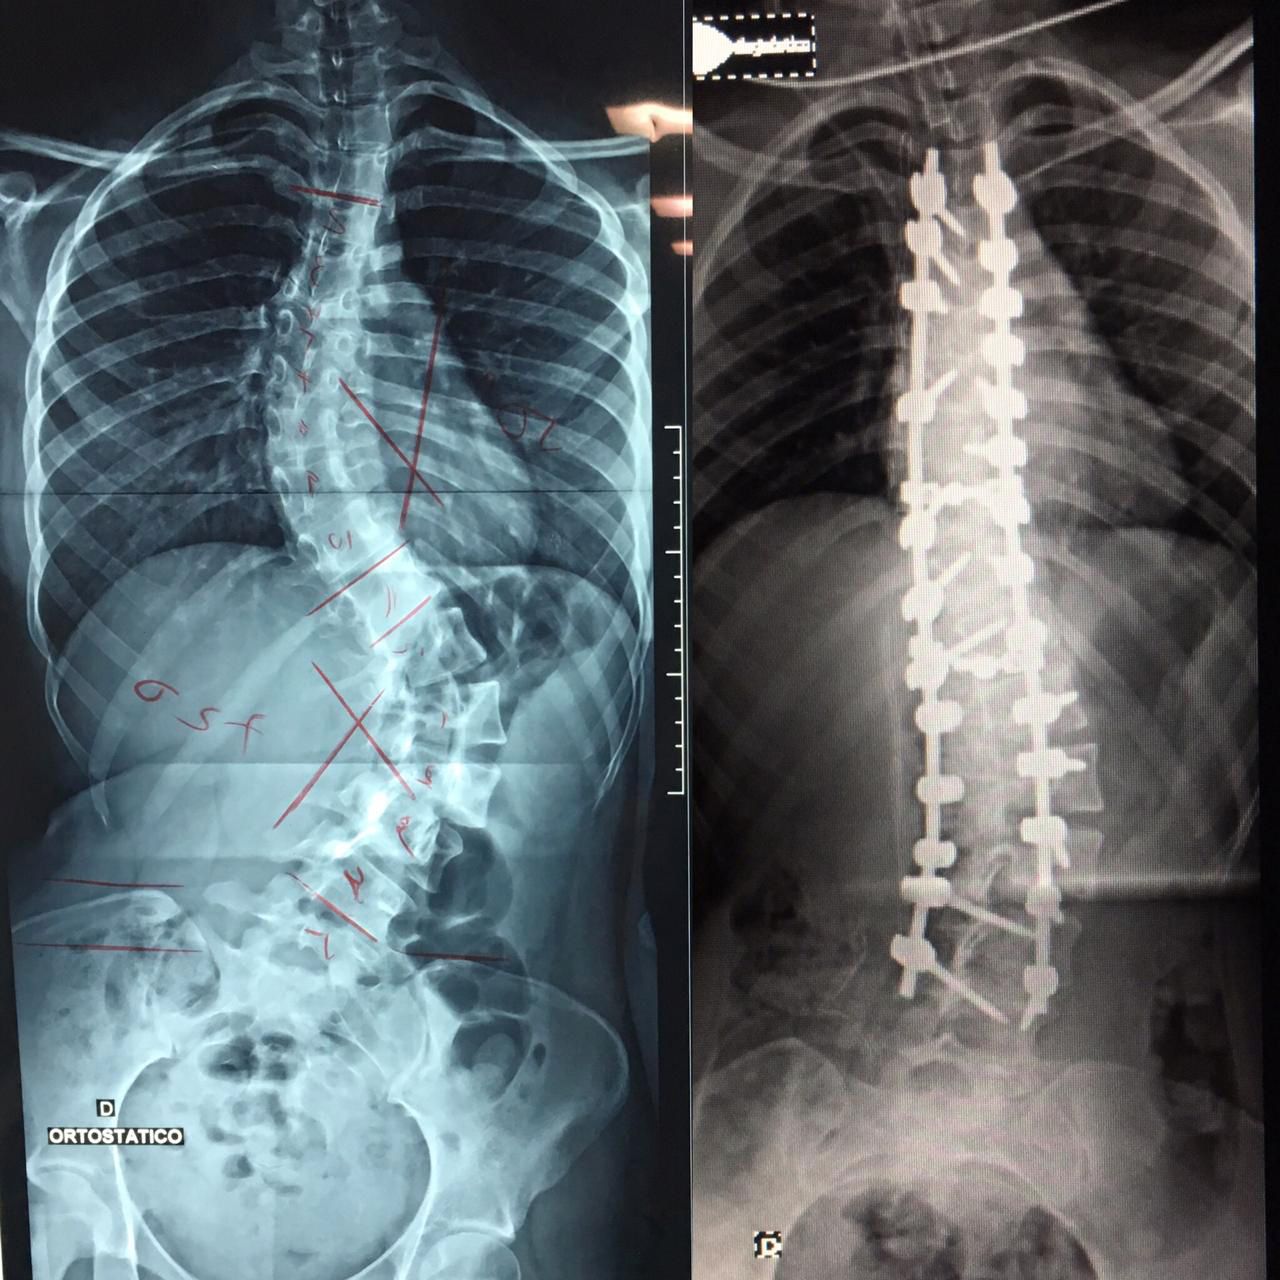

Escoliose

Deformidade da coluna que pode ocorrer por tendências genéticas, síndromes, doenças neurológicas ou desgaste intenso da coluna. Quando diagnosticada precocemente, deve ser acompanhada pois em alguns casos o uso de colete pode ser prescrito. Em casos onde há progressão da deformidade, compressão de nervos, dor intratável, pode-se instituir cirurgias corretivas para a deformidade.